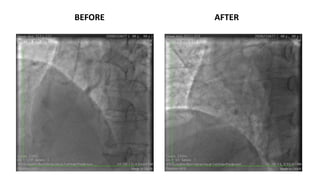

BEFORE AFTER

balloon 2.0/20

POBA LAD